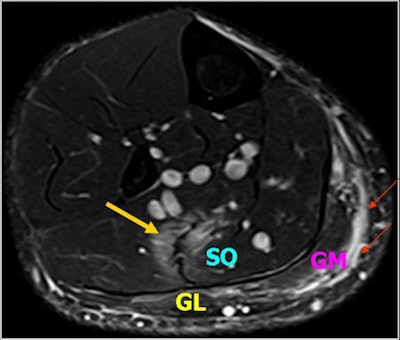

"Fluid-sensitive MR sequences are suitable for detecting edematous changes in the muscles," noted lead author Dr. Daichi Hayashi, PhD, a research assistant professor of radiology at Boston University School of Medicine in the U.S. "T1-weighted sequences are used to differentiate between hemorrhage/hematoma and edema."

Over recent years, MRI has become a valuable tool for evaluation of traumatic muscle injuries, especially among football players, dancers, track and field athletes, and other competitive athletes. Under normal circumstances, images from only the affected leg are acquired using a surface coil, but the appropriate coil should be selected to obtain the desired field-of-view. Imaging of the contralateral leg is performed in exceptional cases only (e.g., bilateral injury).